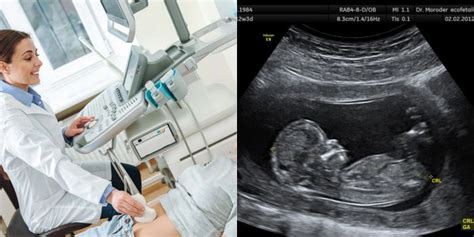

Nėštumą galima nustatyti ir atlikus ankstyvąją echoskopiją. Tiesa, ankstyvoji echoskopija retai atliekama siekiant tiesiog patvirtinti nėštumą.

11-13 nėštumo savaitę atliekamas detalus ultragarsinis tyrimas. Nustatoma preliminari gimdymo data. Apžiūrimos pagrindinės kūno dalys, smegenų struktūra, ieškoma chromosominėms genetinėms ligoms būdingų žymenų. Bene svarbiausias rodmuo - vadinamosios sprando raukšlės (kitaip - vaiskumo) matmuo.

Atliekant ultragarsinį tyrimą 18-20 savaitę matuojamas vaikelio dydis, įvertinama placentos vieta, vaisiaus vandenų kiekis, apžiūrima vaisiaus širdis, kaukolė, vidaus organai. Pagal vaisiaus matmenis apskaičiuojamas vaisiaus gestacinis amžius.